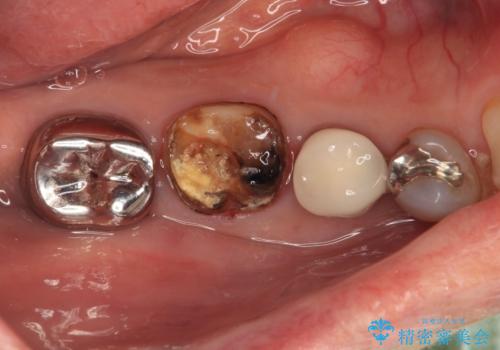

- 奥歯の銀歯に穴が空いてしみるとのことで来院された患者様です。

長年が経過して、徐々に穴が空いてきていたが、最近しみるようになったとのことでした。

痛みの感じ方に異常な所見は認められなかったため、オールセラミッククラウンにて補綴治療を行うこととしました。

銀歯を外したところ、非常に大きなむし歯が認められましたが、神経組織には及んでおらず、速やかにオールセラミッククラウンによる補綴治療を行いました。